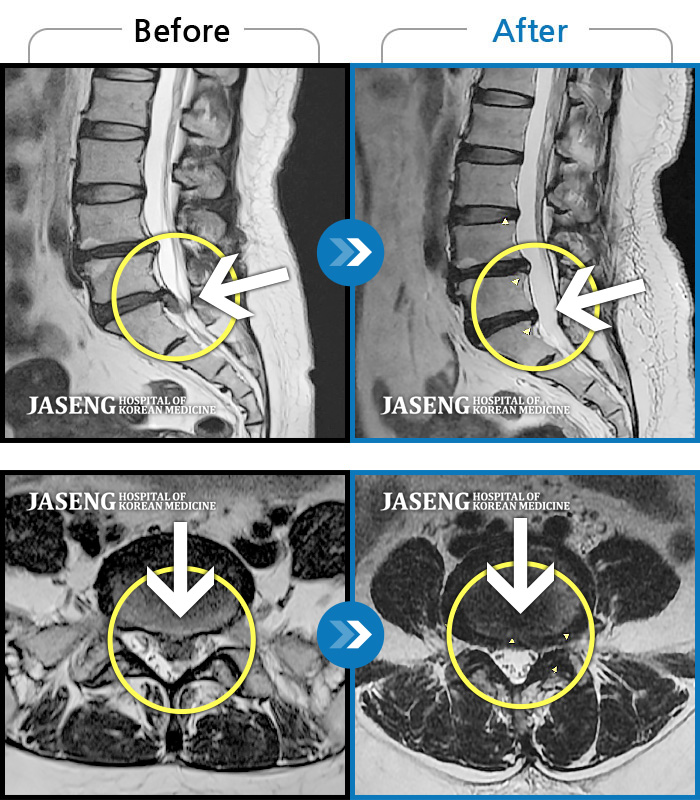

내일이면 퇴원이다. 3월부터 주위에서 허리통증 치료 잘 한다는 통증의학과ㆍ신경외과ㆍ정형외과 병원 3곳을 돌아다니며 허리 신경주사 12번 ,도수치료 10번, 물리치료 등등 정알 여러가지를 받았다. 그러나 치료와 처방 받은 진통제만으로는 일상생활을 하기가 많이 힘들었다. X레이 사진으로 확인한 척추 전방전위증은 결국은 수술을 받아야 한다고 하였다.

전방전위 대해 알아보다가 자생병원 홈페이지에서 김상돈 병원장님이 임상치료 하셨다는 것을 보고 잠시의 망설임도 없이 전화 예약하고 입원 하게 되었다.

MRI 검사로 정확한 진단을 시작으로 병원장님의 치료를 2주간 받았다. 친절한 설명과 따뜻한 배려로 정말 마음 편하게 치료 받을수 있었다.

극심한 통증으로 입원 첫날에 맞은 진통제 주사는 더 이상 필요없게 되었다 다시한번 김상돈 병원장님께 감사 드립니다.